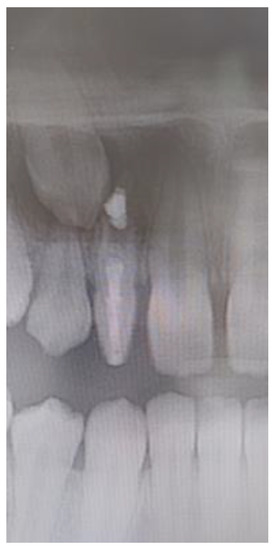

All 13 subjects with peg-shaped PMLI required additional treatment to achieve satisfactory aesthetics and function. Ten (76.9%) of them were treated conservatively by reshaping the tooth crown with composite by a restorative dentist (Figure 3), two (15.4%) subjects were treated with veneers by prosthodontist, and in one (7.7%) subject, the PMLI was extracted by an oral surgeon, space closed orthodontically and canine reshaped in PMLI. 11 (84.6%) subjects treated by restorative dentist, and all subjects treated with veneers by the prosthodontist and oral surgeon were satisfied with the treatment. Two subjects treated by a restorative dentist were dissatisfied with the treatment results and required retreatment.

Figure 3. Reshaping the dental crown with composite by a restorative dentist: (a) before and (b) after buildup.